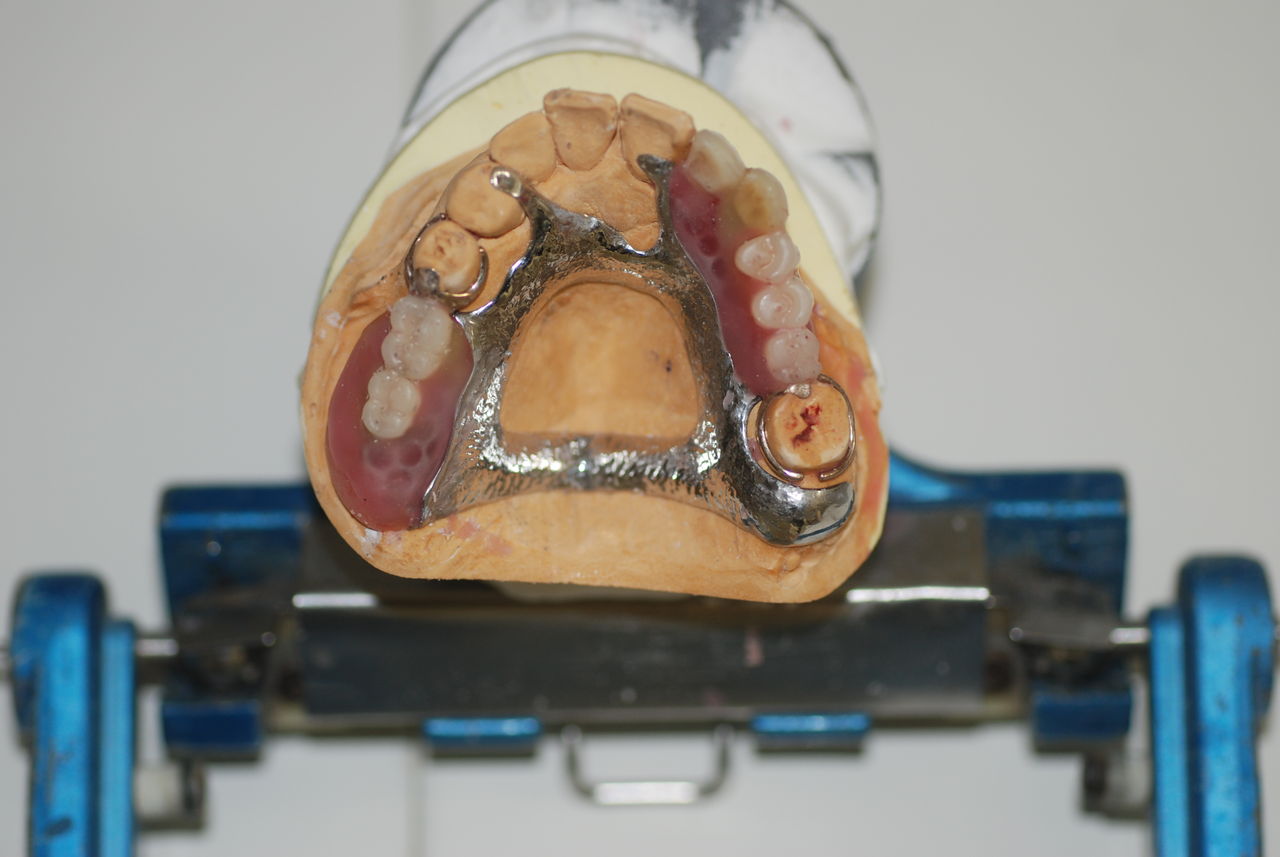

歯周病の疑いで東京のかなり遠方の方が来院されました。

驚くべきことですが、定期検診は受けていたそうです。しかしながら歯周病の指摘は受けたことがないそうです。

何故か?定期検診が虫歯のチェックのみになり、又肝心の歯周病の検査や歯周病の部分の予防や治療のためのブラシの使い方などを学んだ事がないのです。